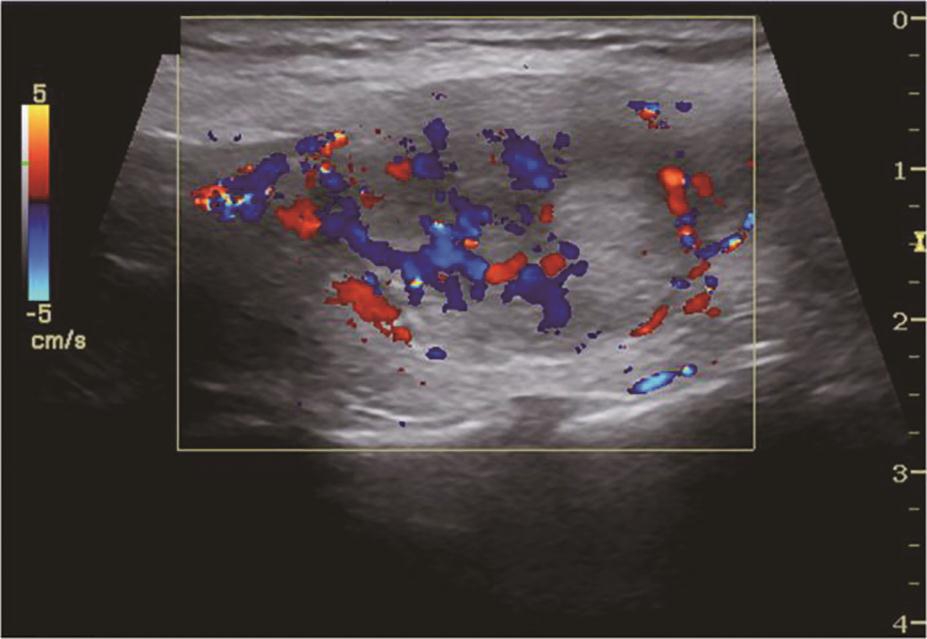

(五)Graves病

甲状腺呈弥漫性、对称性增大,包膜规则。腺体回声因病程和治疗情况而有所不同。未经治疗者,腺体回声均匀减低,少数呈散在、局灶性减低;病程长及反复发作者,腺体回声正常或稍强。腺体内可见多个管状无回声区(血管扩张)。彩色多普勒显示甲状腺内血流信号极为丰富,呈“火海征”(图3)。频谱多普勒可见甲状腺上、下动脉血流速加快,收缩期峰值流速多超过70cm/s(正常为30cm/s)(图4)。

图3右侧颈部纵切面:甲状腺右叶腺体血流信号丰富,呈“火海征”